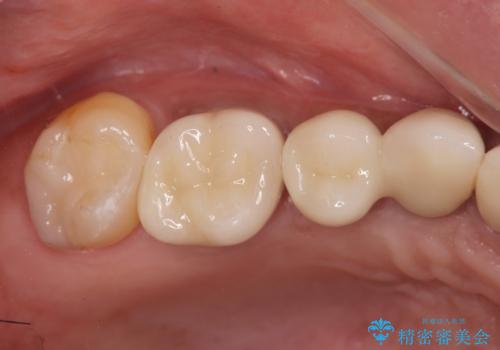

見た目が白くなり喜んでいただけただけでなく、しっかりとした噛めるようになり食事を不安なく楽しんでいただけるようになりました。